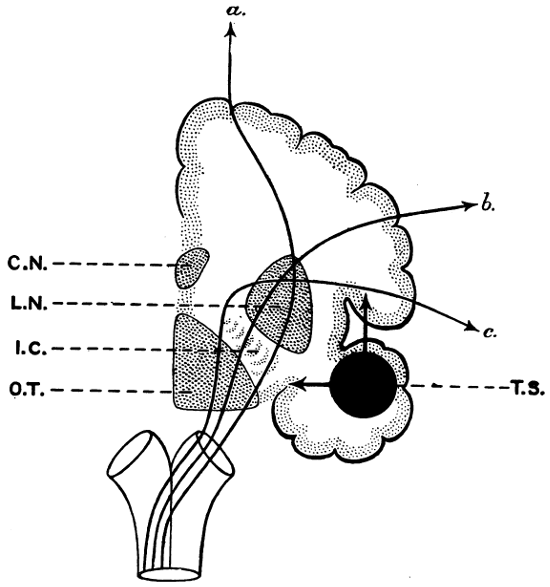

| 69. The visual paths | 223 |